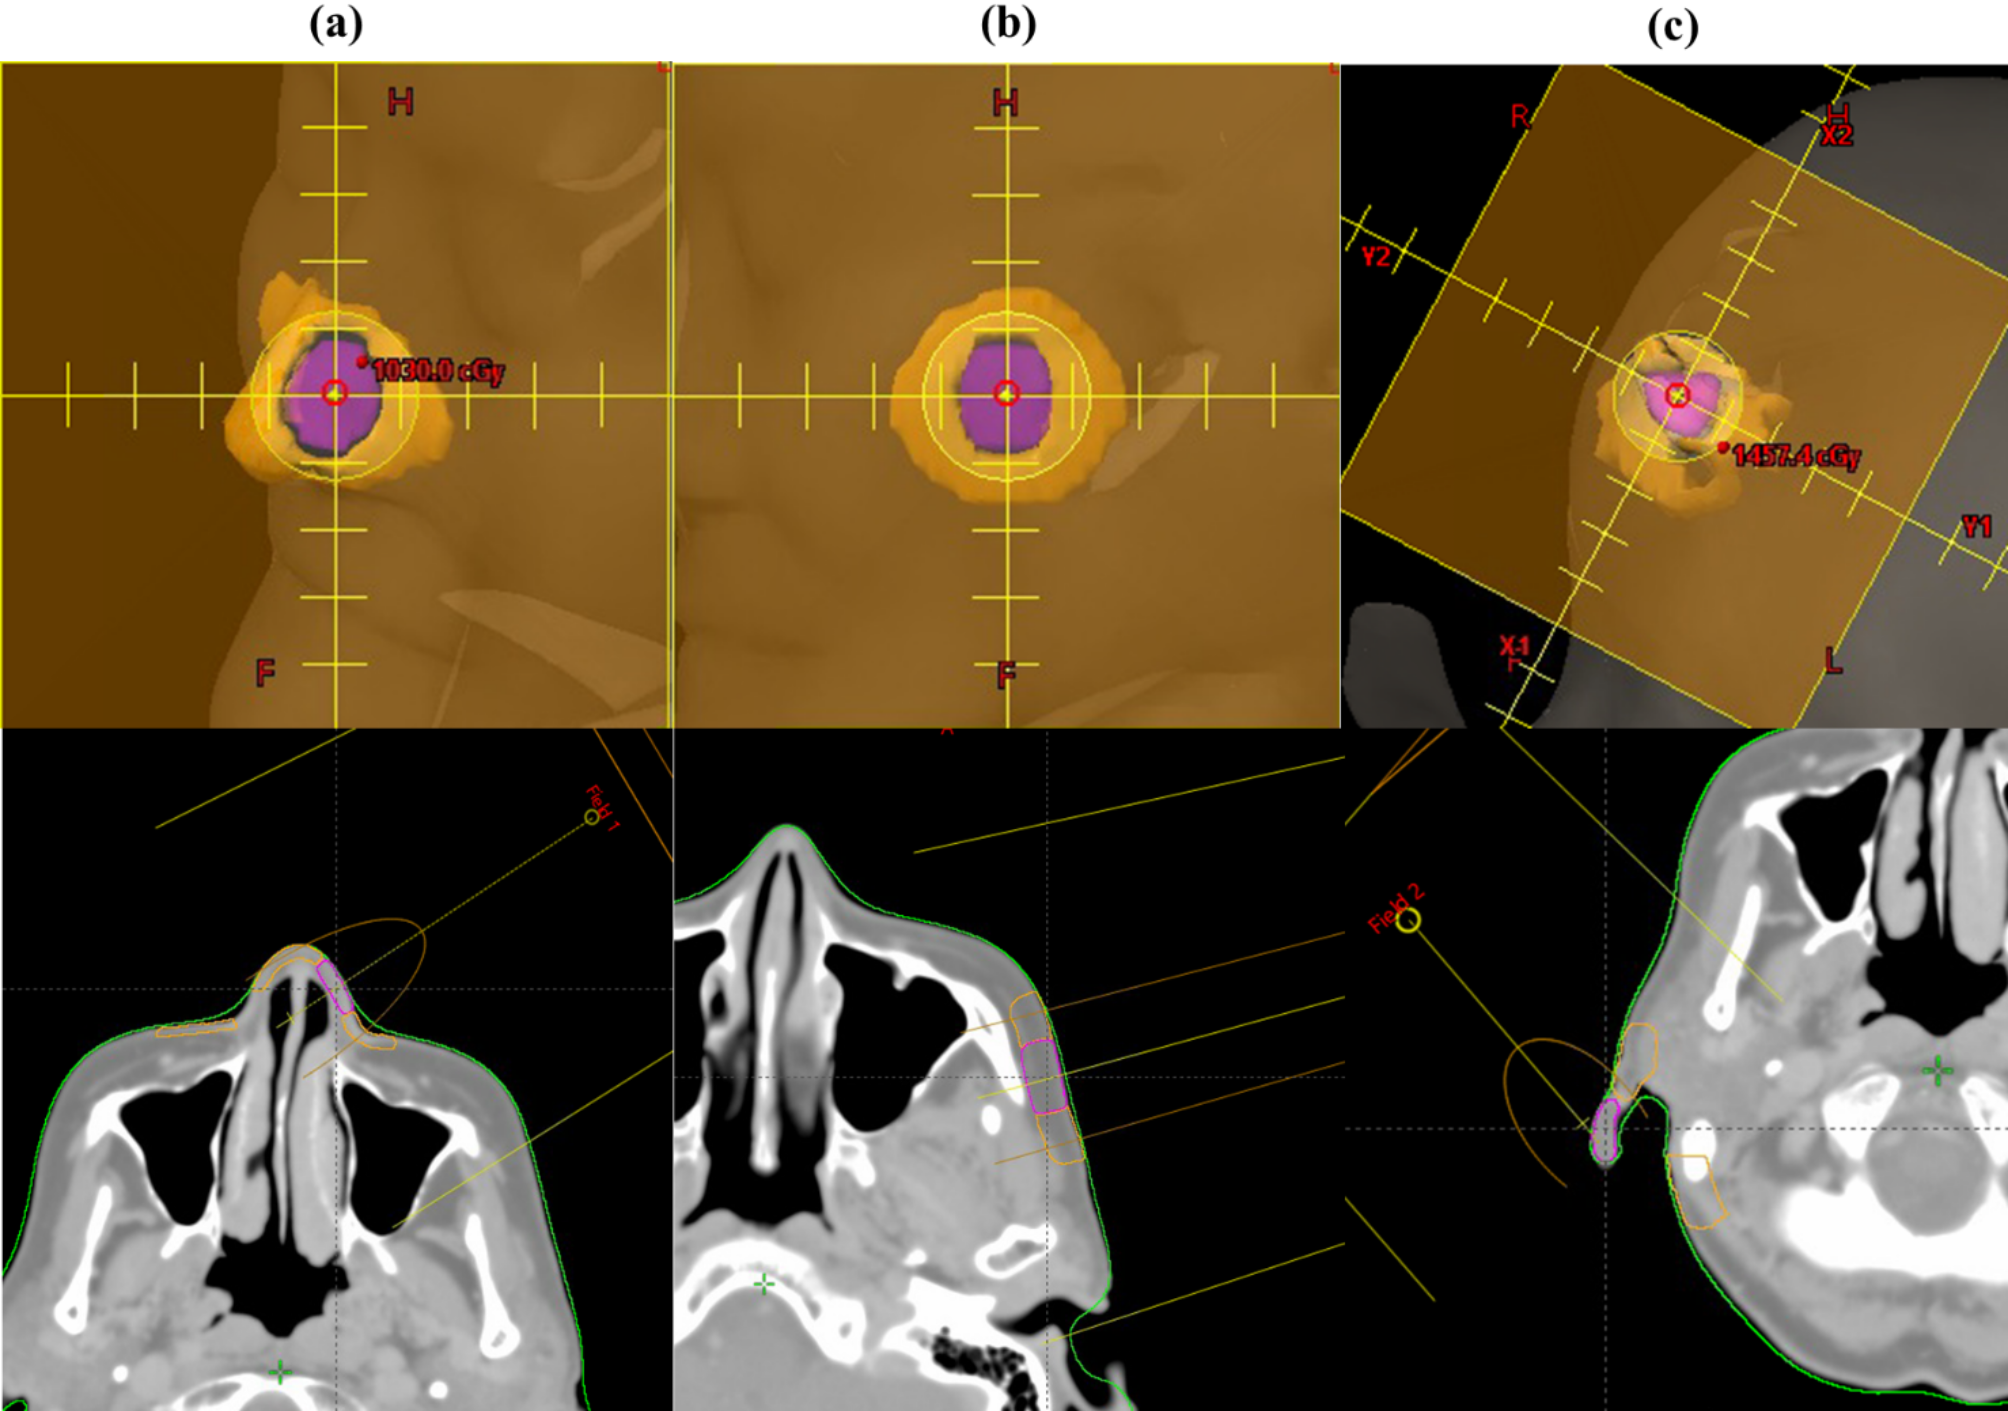

Fig. 2

Beams-eye-view diagrams and axial plane images of the planning target volumes (Magenta) and surrounding normal volumes (Yellow) for representative (a) nose, (b) cheek, and (c) earlobe treatment cases. The images were created using Eclipse version 15.6 (Varian, USA).